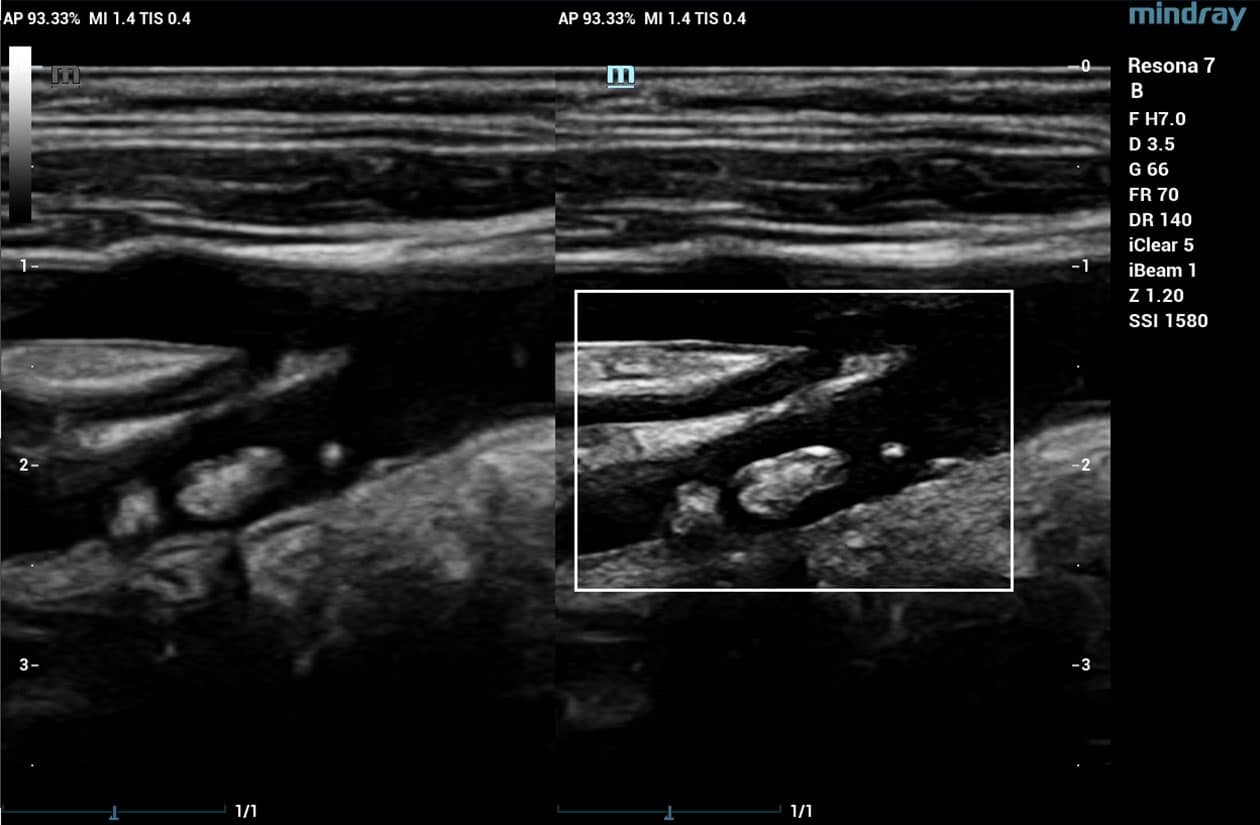

HD Scope

HD Scope is an advanced B-mode image processing technique that focuses additional imaging resources within a specified region of interest (ROI), analyzes the received channel data in unique ways, and applies various filtering and processing algorithms. This results in enhanced contrast resolution within the ROI based on the acoustic characteristics of varying tissue types.